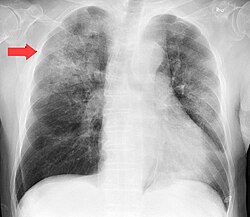

Chest X-ray of a pneumonia caused by influenza and Haemophilus influenzae, with patchy consolidations, mainly in the right upper lobe (arrow)

X-ray presentations of pneumonia may be classified as lobar pneumonia, bronchopneumonia, lobular pneumonia, and interstitial pneumonia. Bacterial, community-acquired pneumonia classically show lung consolidation of one lung segmental lobe, which is known as lobar pneumonia. However, findings may vary, and other patterns are common in other types of pneumonia. Aspiration pneumonia may present with bilateral opacities primarily in the bases of the lungs and on the right side. Radiographs of viral pneumonia may appear normal, appear hyper-inflated, have bilateral patchy areas, or present similar to bacterial pneumonia with lobar consolidation. Radiologic findings may not be present in the early stages of the disease, especially in the presence of dehydration, or may be difficult to interpret in the obese or those with a history of lung disease. Complications such as pleural effusion may also be found on chest radiographs. Laterolateral chest radiographs can increase the diagnostic accuracy of lung consolidation and pleural effusion.